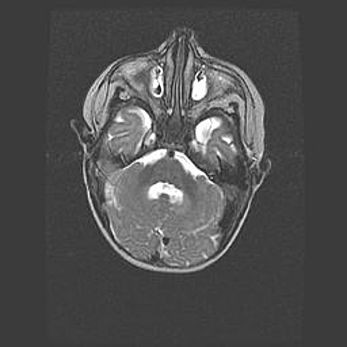

Мальформация Денди-Уокера. Киста задней черепной ямки.

Агенезия мозолистого тела.

Возраст: 2,5 месяца

Вес: 2420 г

Пол: женский

Окружность головы: 37 см

Срок гестации: 32 недели

Мальформация Денди—Уокера — редкий вид патологии ЦНС, представляющий собой врожденный порок развития каудального отдела ствола и червя мозжечка, ведущий к неполному раскрытию срединной (Мажанди) и латеральных (Лушка) апертур IV желудочка мозга. Для этогно синдрома характерна триада симптомов: гипотрофия червя мозжечка и/или полушарий мозжечка, кисты задней черепной ямки, гидроцефалия различной степени. В 70% случаев порок сочетается и с другими аномалиями головного мозга, в частности с агенезией мозолистого тела.